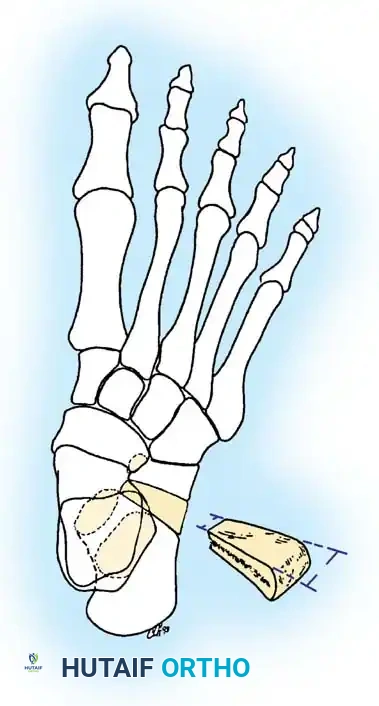

2. Lateral Column Lengthening (Anterior Calcaneal Osteotomy)

Described by Dillwyn Evans and modified by Mosca, this procedure corrects midfoot abduction and restores the talonavicular joint congruency by lengthening the lateral column.

* Osteotomy: Perform a transverse osteotomy of the anterior calcaneus approximately 1.5 cm proximal to the CC joint line. Use an oscillating saw, taking care not to breach the medial calcaneal cortex entirely, leaving a periosteal hinge.

- Distraction: Insert a lamina spreader into the osteotomy. Gently distract the site while observing the medial longitudinal arch. The forefoot will adduct, and the talonavicular joint will reduce.

- Grafting: Harvest a tricortical iliac crest bone graft (or use structural allograft) tailored to the exact dimensions of the distracted gap (typically 8 to 12 mm). Tamp the graft into place.

- Fixation: While the graft is often stable under compression, supplemental fixation with a cervical plate or a single compression screw is highly recommended to prevent graft extrusion or nonunion.